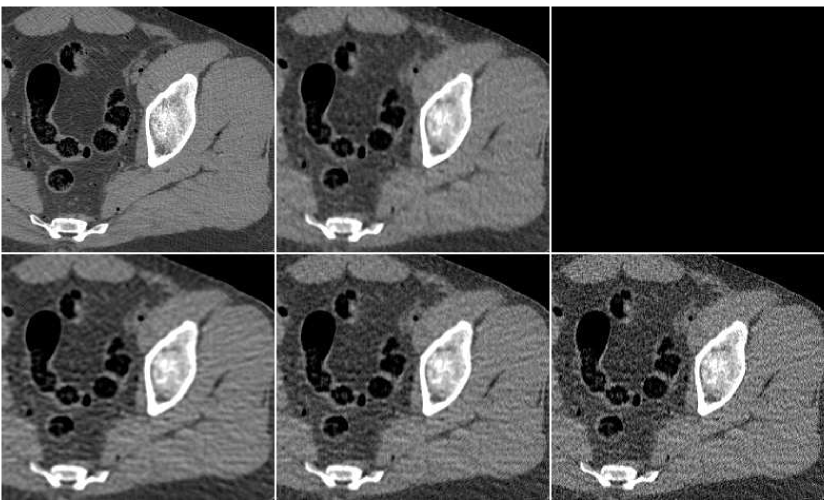

We conducted numerical experiments to demonstrate the proposed method using the same setup as in the FBP experiment. Training data for the ANN was obtained using a data-set of axial male thighs section images. For each, an initial image is computed with the FBP algorithm using a sinogram filter with cut-off frequency value of (see Figure 5). The PWLS algorithm is implemented as described in Section II-B, with parameters , . We have performed iterations, saving an image version every iterations - overall we have a sequence of images. In practice, we use three images out of this sequence, namely those from iterations 20, 60 and 80. From the first and the third images, neighborhoods of radius ( pixels) were taken for the estimation of the pixel value, and the second image contributed a neighborhood of radius ( pixels). Overall, the ANN has inputs. It is set to be a network with neurons in the (single) hidden layer. It has a single output, set to produce only the central pixel of the provided neighborhood. These specific settings were obtained with a manual tuning of the design parameters.

In Figure 10 we display the fusion result along with individual PWLS reconstructions, used in the fusion process. The lower part of the figure contains the absolute-valued error images. The fusion result has a higher visual quality than any of the three underlying images. Comparing to those images, the noise level in the fusion image is the lowest, and the tissue texture is closer to the original. The sharpness is the same as in the lower middle PWLS image. The SNR values (stated in the Figure) also point to the improvement in quality. The SSIM of the fusion image is , while the sequence of PWLS results have the SSIM values of (corresponding to the lower row of Figure 10, left to right). A reconstruction of an additional test image is displayed in Figure 11. The effect of the fusion observed here is similar to the one in the previous reconstruction. We conclude that the ANN-based fusion can contribute also to the iterative reconstruction, without requiring any additional iterations; the computational cost of the fusion, exercised after the reconstruction, is lower by an order of magnitude than that of the iterative process.

In order to test the robustness of the training results, we apply the ANN trained with the thigh sections, for a reconstruction of images of other body parts – sections of the head and the abdomen. Reconstruction results are presented in Figure 13 in the same order as in the previous comparison: middle image in the upper row is the result of fusion, which components are presented in the lower row. The head reconstruction is improved substantially by the fusion process, as visual observation shows. However, the SNR values (given in Table II) point to the favor of the PWLS image corresponding to iterations (lower middle image). The highest SSIM value does belong to the fusion result, though. In the case of the abdomen section, the fusion image is similar to the -iterations version but contains less noise; its quantitative measures are somewhat better than those of the individual PWLS images.